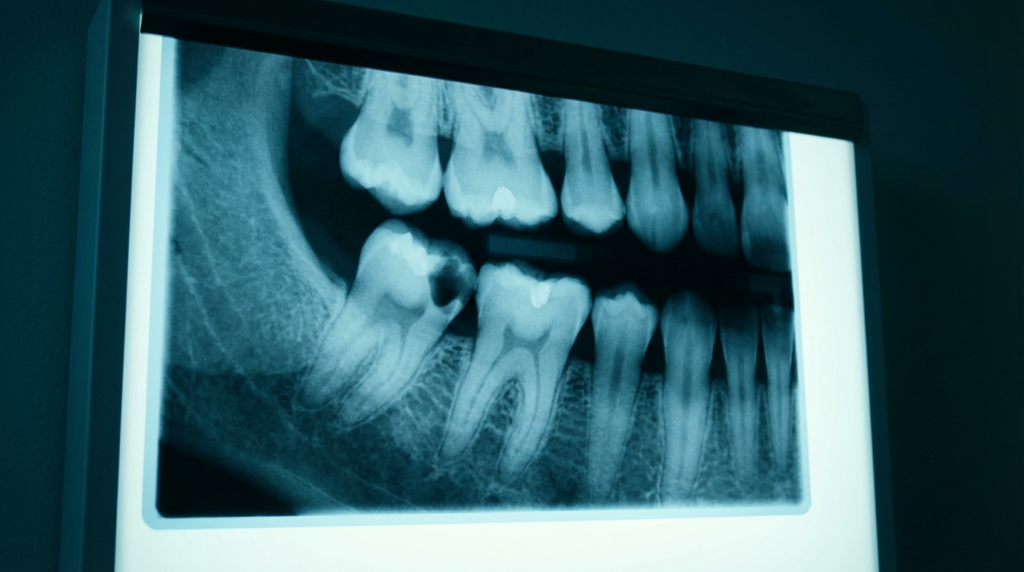

レントゲン検査では、歯の根の周りに大きな感染領域(根尖病巣)が見られます。